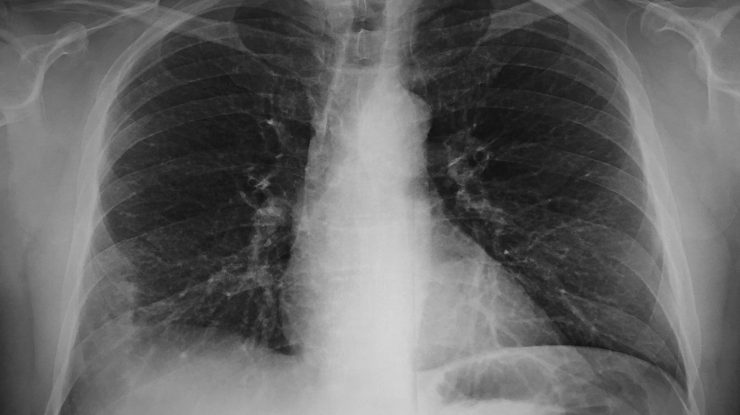

Oamenii de știință americani de la Universitatea din California, San Diego, au dezvoltat nanoroboți care livrează antibiotice direct în plămâni. Acestea sunt mult mai eficiente decât medicamentele convenționale în tratarea unei forme mortale de pneumonie bacteriană.

Cercetarea este publicată în revista Nature Materials. Bacteria Pseudomonas aeruginosa poate provoca o formă acută periculoasă de pneumonie. De obicei, aceasta este tratată cu antibiotice intravenoase, dar adesea acest lucru nu este suficient. Prin urmare, o astfel de pneumonie bacteriană are o rată de mortalitate destul de ridicată.